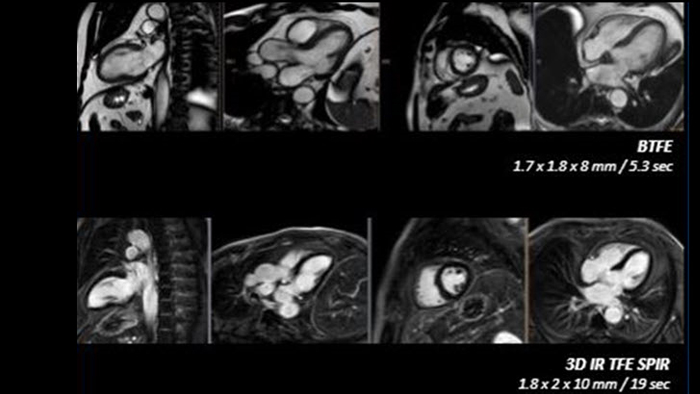

Realize the potential of MR throughout the pathway with ultrafast exams, optimized workflow, high-quality diagnostic imaging and enhanced patient comfort.

Enhance diagnosis confidence and clinical efficiency through superior image quality, advanced quantification tool and automation technology.